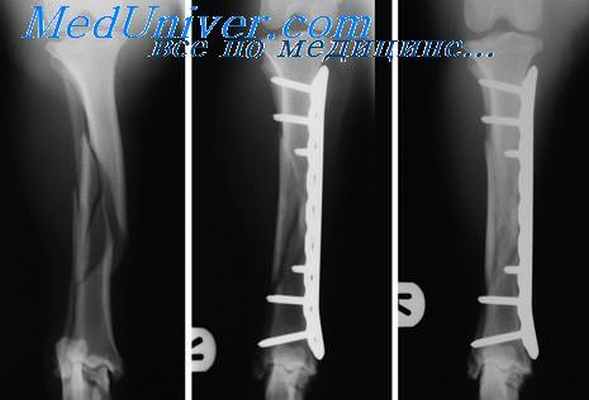

Рентгенологические признаки ложного сустава представлены:

- визуализацией линии незаращения из-за замедленной консолидации

- склерозом концов отломков

- костными наростами в области несращения (при гипертрофическом типе псевдоартроза)

- искривлением оси конечности

- смещением фрагментов

- остеопорозом (разрежением костной ткани)

- асептическими некрозами концов костных отломков, возникновение в последних зон деградации

- обнаружением всех элементов сочленеия в нетипичном месте - суставной впадины, головки кости, синовия, остеофитов при неоартрозе и др.

- устойчивого остеосинтеза – для проведения операции, цель которой – сблизить и зафиксировать отломки, используются металлические элементы. В месте повреждения делается надрез, отломки костей стягивают и соединяют при помощи пластины, стержня, аппарата внешней фиксации или аппарата Илизарова. Непрочное соединение (нестабильный остеосинтез) после хирургического вмешательства – одна из причин ложного сустава, поэтому при выполнении повторной операции уделяют повышенное внимание фиксации;